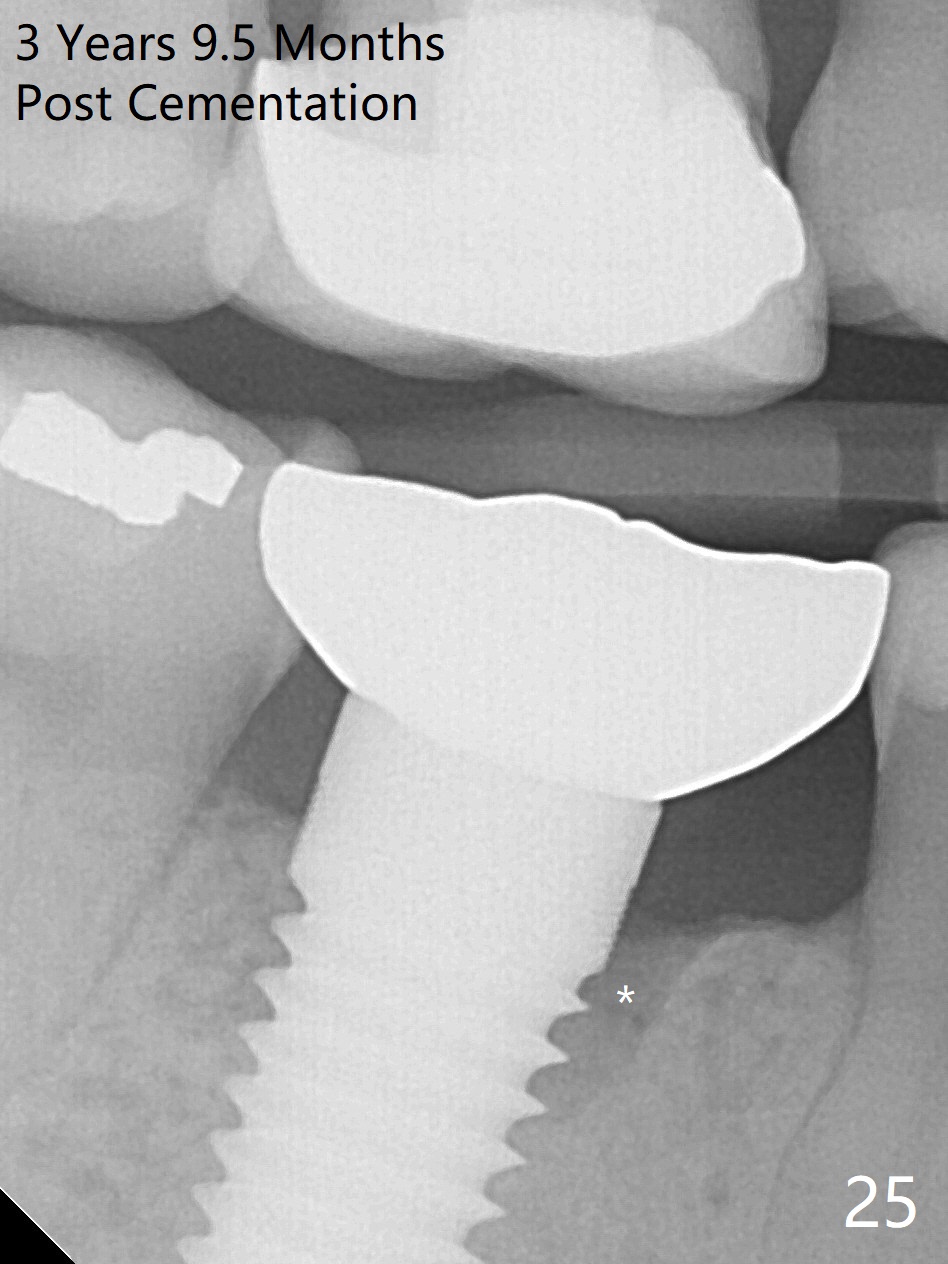

The patient will return for immediate implant at #14. Do not forget placing an implant as palatal as possible. There is no sign of infection at #30 three years 9.5 months post cementation because of water pik for #3 endo failure (Fig.25,26).